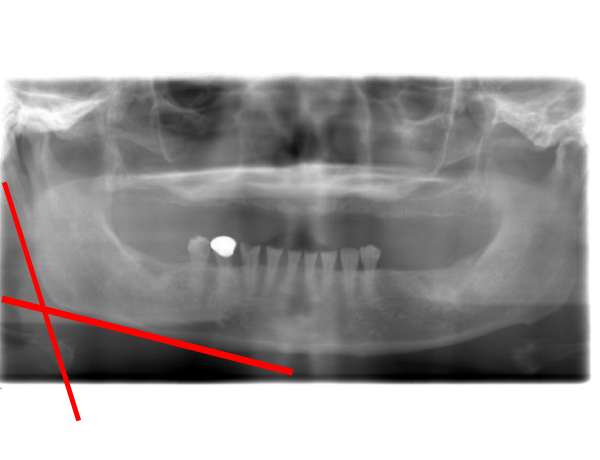

レントゲンの評価

下あごの骨がしっかりとたくさん残っており、いかにも噛み合わせが強そうです。あごの骨の角度が直角に近いので、がっしりとした顎ということが予想されます。